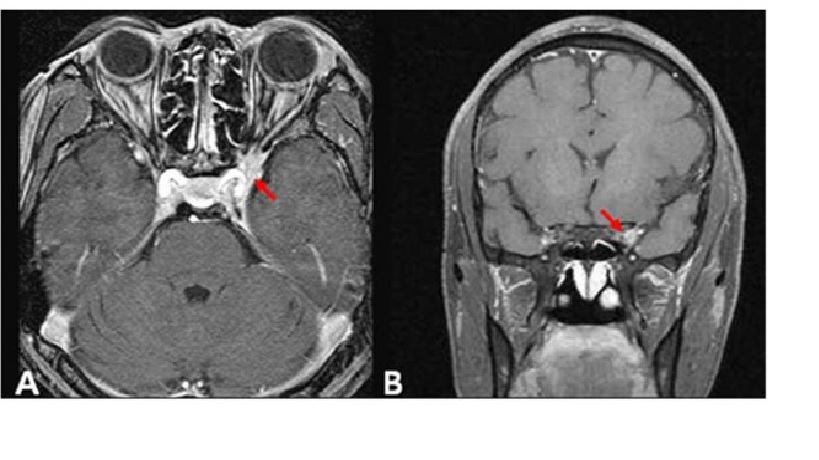

Cavernous sinus syndrome do sarcoidosis

Hình ảnh Gadolinium-enhanced T1-weighted axial (A) và coronal (B) cho thấy một khối tăng cường liên quan đến xoang hang trái. Hình ảnh Gadolinium-enhanced T1-weighted axial (C) sáu tháng sau khi điều trị bằng steroid